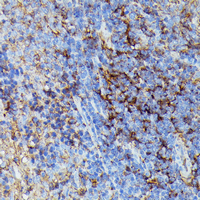

Immunohistochemical analysis of HLA-B staining in rat spleen formalin fixed paraffin embedded tissue section. The section was pre-treated using heat mediated antigen retrieval with sodium citrate buffer (pH 6.0). The section was then incubated with the antibody at room temperature and detected using an HRP conjugated compact polymer system. DAB was used as the chromogen. The section was then counterstained with haematoxylin and mounted with DPX.

Immunohistochemical analysis of HLA-B staining in rat spleen formalin fixed paraffin embedded tissue section. The section was pre-treated using heat mediated antigen retrieval with sodium citrate buffer (pH 6.0). The section was then incubated with the antibody at room temperature and detected using an HRP conjugated compact polymer system. DAB was used as the chromogen. The section was then counterstained with haematoxylin and mounted with DPX.